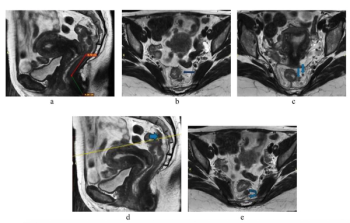

Abbreviated MRI demonstrated a 95.3 percent specificity for rectal cancer and provided strong agreement with the full MRI protocol for T staging and detection of extramural venous invasion, according to newly published research.